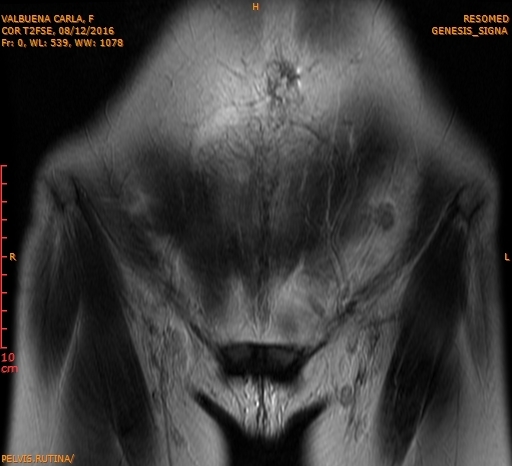

During my annual routine check-ups, in order to be ready to search for our second baby, precisely on the day that I was doing my breast ultrasound (because I was still breastfeeding my daughter), I asked my colleague to check my uterus with the ultrasound equipment. An image appeared and the doctor asked to evaluate it with an MRI. To our surprise, the results confirmed that I had a tumor and had to have an immediate surgery.

Therefore, on Tuesday November 22, 2016 I had to undergo surgery, and that day God changed my life plans. The doctors had to practice a hysterectomy, take out my ovaries, the uterus. They had to remove part of my intestine and my appendix as well, due to the fact that the biopsy showed that it was a leiomyosarcoma with metastasis. These were days of great anguish and worry, while we awaited the results of the definitive biopsy, both for myself and my family, as a doctor I understood how risky my situation was.

I definitely consider that God has given me a second chance, due to the fact that I had surgery on time, which is not frequent with this type of tumors. Usually they are not surgical. They usually have a large size and when people go see their doctors, and  it is mainly for secondary reasons related to the tumor. In my case it measured 10 cm, which is a small measure for this type of cancer. However it proved to be aggressive, since it presented metastasis all around.